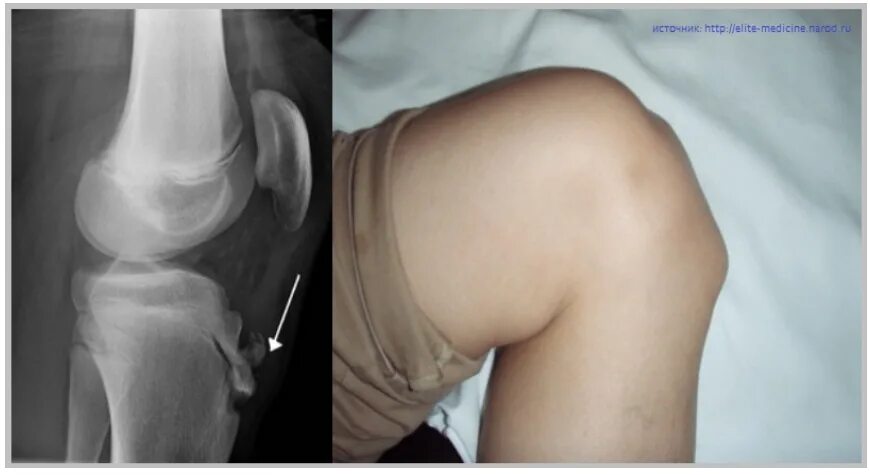

Нестабильность коленного сустава симптомы